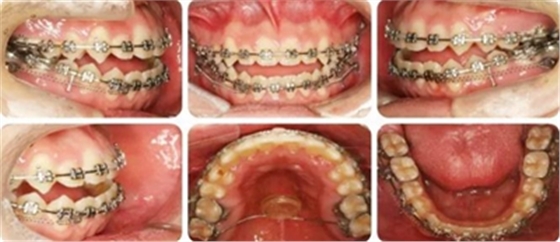

結(jié)束時,可見前牙覆合覆蓋正常,上下牙列排齊,雙側(cè)尖磨牙達到中性關(guān)系。

高角反頜伴開頜病例,多采用正畸正頜聯(lián)合治療。但該患者為直面型,下牙列輕度擁擠,下前牙直立,且年齡較小,手術(shù)治療非首選。采用種植釘內(nèi)收下前牙代償性治療前牙反合。而且需要拔除阻生智齒減小遠(yuǎn)移下牙列的阻力。

羅晨醫(yī)生:我今天展示的病例,技術(shù)創(chuàng)新在于種植釘整體遠(yuǎn)移下頜全牙列。臨床正畸治療中,對于反頜伴開頜的患者,一直是令人困擾的難題。以往的上頜骨嚴(yán)重發(fā)育不足的患者,只能通過正頜手術(shù)進行改善,但一來患者比較痛苦,二來費用較高,

給患者帶來很大的負(fù)擔(dān)。而本病例通過下頜頰棚區(qū)植入微種植釘,整體將下頜牙列內(nèi)收,引起下頜骨逆時針旋轉(zhuǎn),開合和反合得到了糾正,達到了良好的效果。